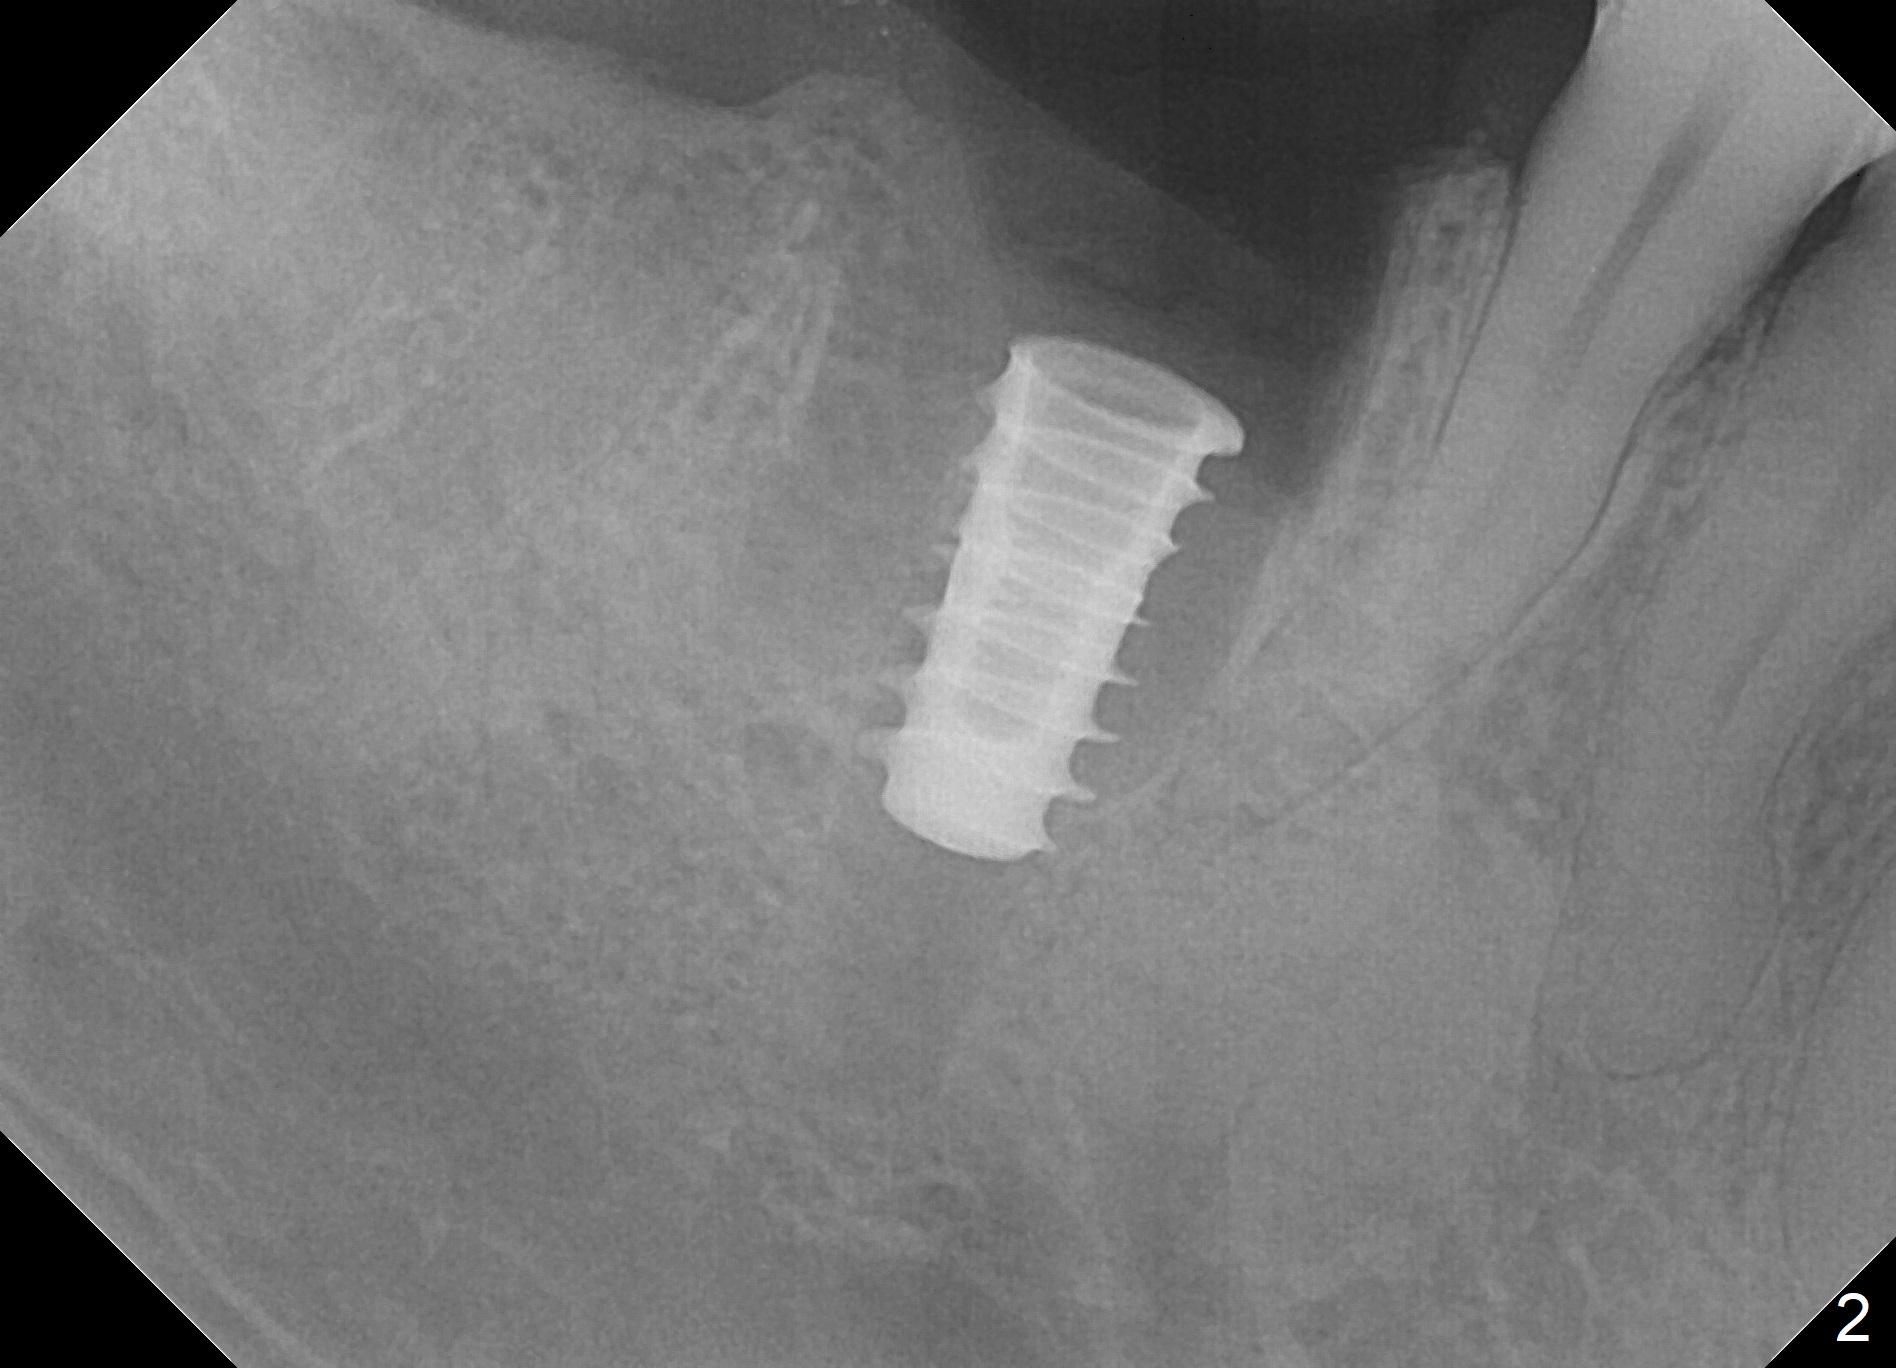

Extraction is difficult due to hard bone and brittle, curved roots of the tooth #30; initial depth in the septum is 14 mm (gingival level, Fig.1). Then the depth increases to 17 mm; with sequential osteotomy using 2.8 mm to 4.8 mm Magic Drills (MD), a 5x9 mm dummy implant is placed incompletely due to hard bone (Fig.2). After use of 5.3 mm MD for ~ 15 mm, the dummy implant is placed to the depth (Fig.3). The definitive IBS implant (5x13 mm) is placed with 50 Ncm; a 6.5x5.7(4) mm abutment is placed with allograft filling the gap (* and arrow).